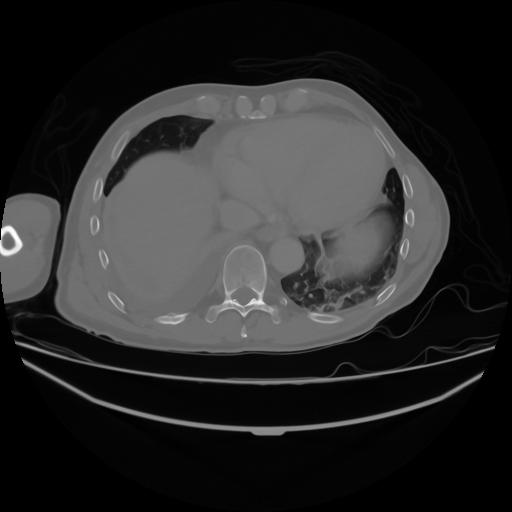

4 CUERPO,CE,Axial,3.0,CUERPO,,